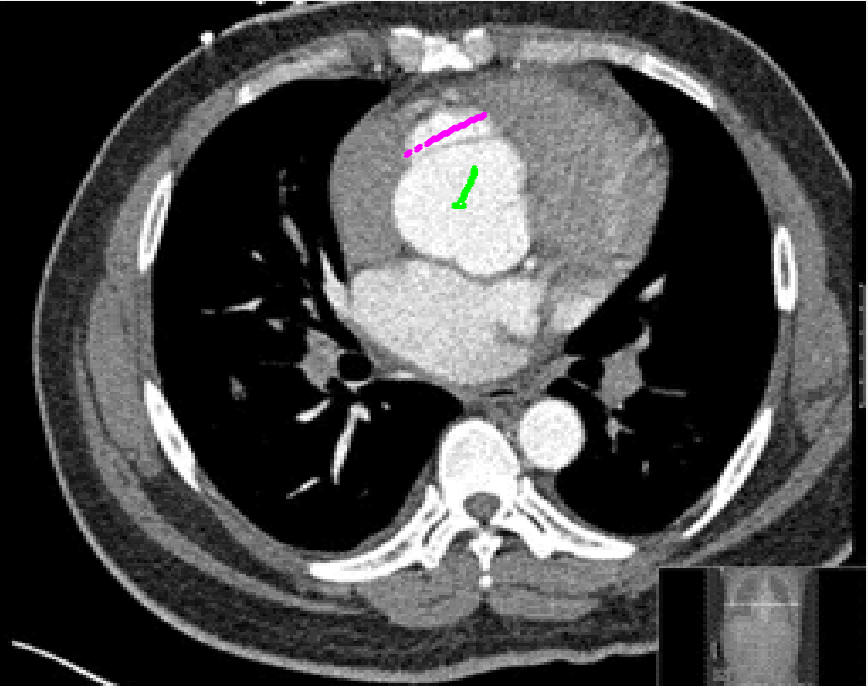

Refer to caption

Figure 6: (Left to right:) original image, \mathcal{M} (green) and 𝒜𝒜\mathcal{AM} (pink), segmentation result just using marker set, 𝒟AM(x,y)subscript𝒟𝐴𝑀𝑥𝑦\mathcal{D}_{AM}(x,y) using anti-markers, segmentation result using anti-markers. For these μ=1,λ1=λ2=5,θ=25formulae-sequenceformulae-sequence𝜇1subscript𝜆1subscript𝜆25𝜃25\mu=1,\lambda_{1}=\lambda_{2}=5,\theta=25.

where α~~𝛼\tilde{\alpha} is a tuning parameter. We choose α~=200~𝛼200\tilde{\alpha}=200 throughout. This distance term ensures rapid decay of the penalty away from the set 𝒜𝒜\mathcal{AM} but still enforces high penalty around the anti-marker set itself. See Figure 6 where a segmentation result with and without anti-markers is shown. As 𝒟AM(x,y)subscript𝒟𝐴𝑀𝑥𝑦\mathcal{D}_{AM}(x,y) decays rapidly from 𝒜𝒜\mathcal{AM}, we do require that the anti-marker set be close to the blurred edge and away from the object we desire to segment.